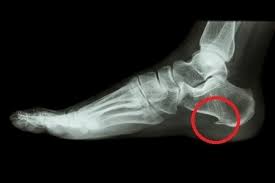

整形外科に行くとまずはレントゲン撮影を行うことになるでしょう。

かかとの骨に「骨棘(こつきょく)」と言って骨のトゲがないかどうかを調べることになります。

足底筋膜炎が発症してから時間の経過が長ければ、骨棘が形成されていることも多いからです。

レントゲンで骨棘が見つかり、痛みが引かない場合は最終的に手術となるでしょう。

骨棘を形成してしまったので、外科的な処置で痛みの改善となりますが、骨棘を作ってしまった原因を考えて処置をしないと再発の恐れもあるのでご注意ください。

骨棘が発生する足底筋膜炎の場合ですとふくらはぎの筋肉が強く関与していて慢性的に引っ張りを強くしていたために骨のトゲが作られてしまうような現象を起こしてしまいます。